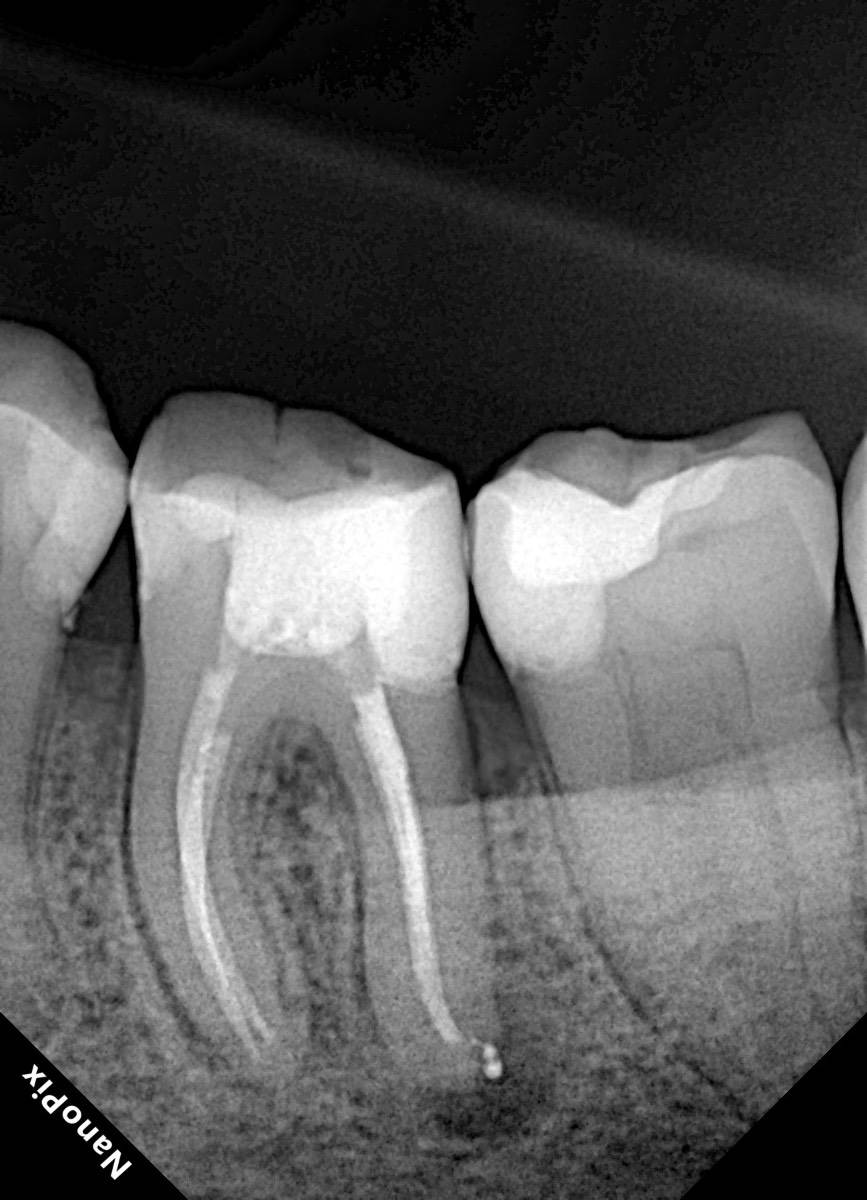

Гарриевич Опубликовано 31 января Автор Поделиться Опубликовано 31 января Когда в твоем кресле оказывается пациент с редким заболеванием «стоматолог-терапевт» работать всегда… легче. Именно! Потому что ты на 100% уверен, что этот человек понимает разницу между «гарантия» и «прогноз», а он на 100% уверен, что ты тот кто ему нужен. Зуб 4.7 со сложной анатомией, ступенькой в мезиальной системе, двойным изгибом, пропущенным каналом и апикальным периодонтитом. Реколл 1 год И сам осмотр через 1 год 4 1 1 Ссылка на комментарий

Гарриевич Опубликовано 18 марта Автор Поделиться Опубликовано 18 марта В 13.03.2026 в 15:26, Doc сказал: Круто! То, что вынимается, доктору вернуть надо или в металлолом сдать? :))) Обычно мы сдаем в чернмет, какие никакие деньги)) Реколл 3 года 1 Ссылка на комментарий